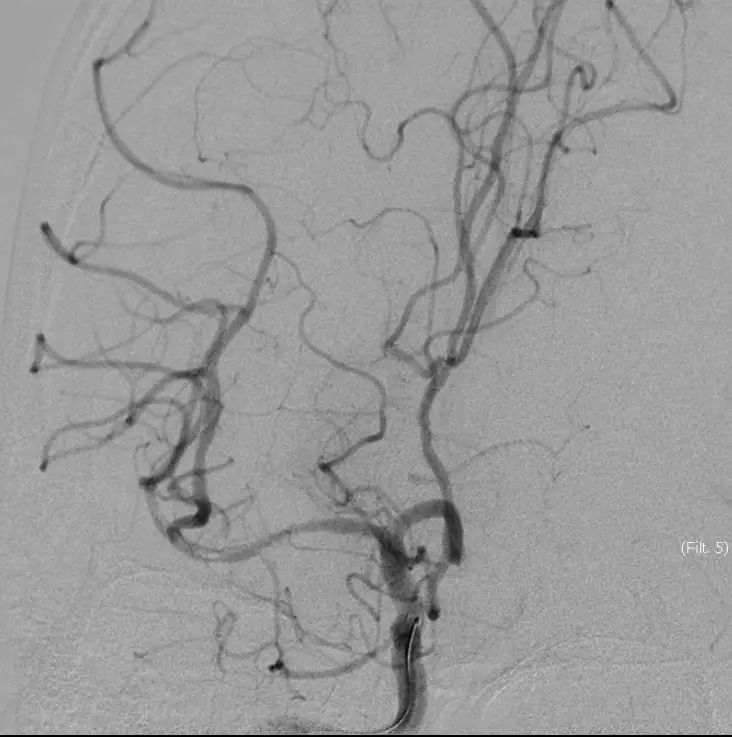

5MIN后

10MIN后

再次与家属沟通病情,交代支架植入风险,家属表示理解,准备支架解脱

5MIN后

再次观察10MIN后